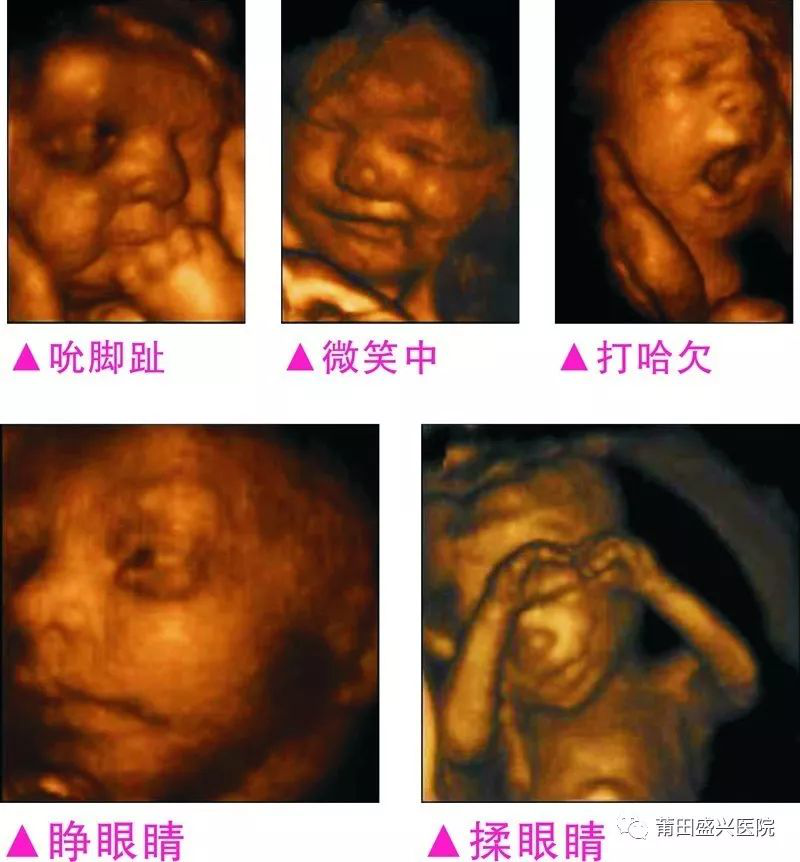

【生命初奇】盛興醫(yī)院讓您更早見(jiàn)識(shí)寶寶的調(diào)皮可愛(ài)

您一定不知道寶寶有多調(diào)皮可愛(ài)

你一定不知道寶寶這么小就有這么多表情

這個(gè)視頻是盛興醫(yī)院超聲科同事手機(jī)錄下來(lái)的,是一個(gè)孕婦懷孕24周2天來(lái)做E8四維彩超檢查時(shí)的記錄。

四維容積成像技術(shù),智能光源系統(tǒng)展現(xiàn)梯度亮度,渲染畫(huà)面,提高容積成像品質(zhì),高清顯示腹中寶寶的實(shí)時(shí)動(dòng)態(tài)影像,完整記錄寶寶的一舉一動(dòng),讓準(zhǔn)爸媽與寶寶Di一次幸福“見(jiàn)面”,更可刻錄成高清視頻,送給未來(lái)寶寶的珍貴禮物。